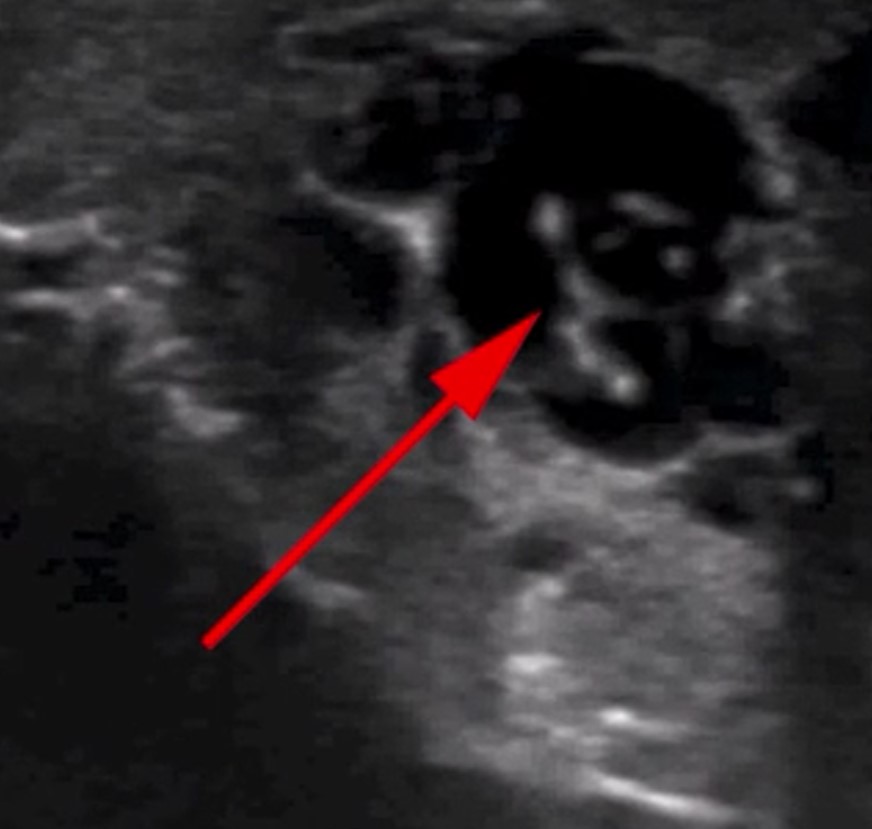

İngiliz Daily Mail gazetesinde yer alan habere göre, doktorlar hastanın skrotumunda hareket eden doğrusal yapılar keşfetti.

Nadir görülen enfeksiyon, New England Journal of Medicine tarafından yayınlanan bir vaka raporu ile ortaya çıktı. Hastayı muayene eden Max Süper Özel Hastanede kıdemli tıbbi danışman olan Dr. Amit Sahu, ultrasonda 'doğrusal yapıların hareket ettiğini' söyledi.

Sahu gözlemledikleri hareket eden doğrusal yapılar için 'dans edecen düzinelerce solucan' ifadesini kullandı. Sahu, 'Lenf sistemine göç ederek kanalların genişlemesine ve işlev bozukluğuna neden oldular' dedi.

Ultrasondan sonra doktorlar skrotumdan sıvı örneği aldı ve mikroskop altında inceledi.